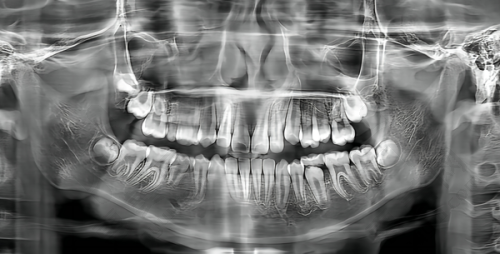

重庆理想口腔医院是重庆旗下口腔连锁医院之一,位于长寿区桃园西一路222号9楼(中央公园旁)。它是集急救、临床、教学和科研于一体的口腔单位。医院规模不小,住院部有10多张床位,门诊有20余张牙科治疗椅。而且正畸分公司配备了口腔CBCT机,这能为口腔疾病的诊断和治疗提供完整的信息。